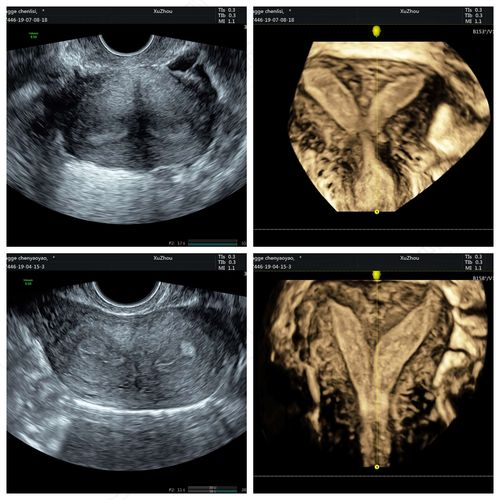

完全性纵隔子宫是指子宫的中间有一个纵隔把子宫分成两半,而且纵隔的末端到达或者超过宫颈口,有的时候甚至到达宫颈外口,医生做妇科检查的时候感觉到像是两个宫颈。这样的患者往往会伴有反复的流产、早产,以及胎膜早破等现象,所以最好进行手术治疗,否则会影响怀孕和生育。